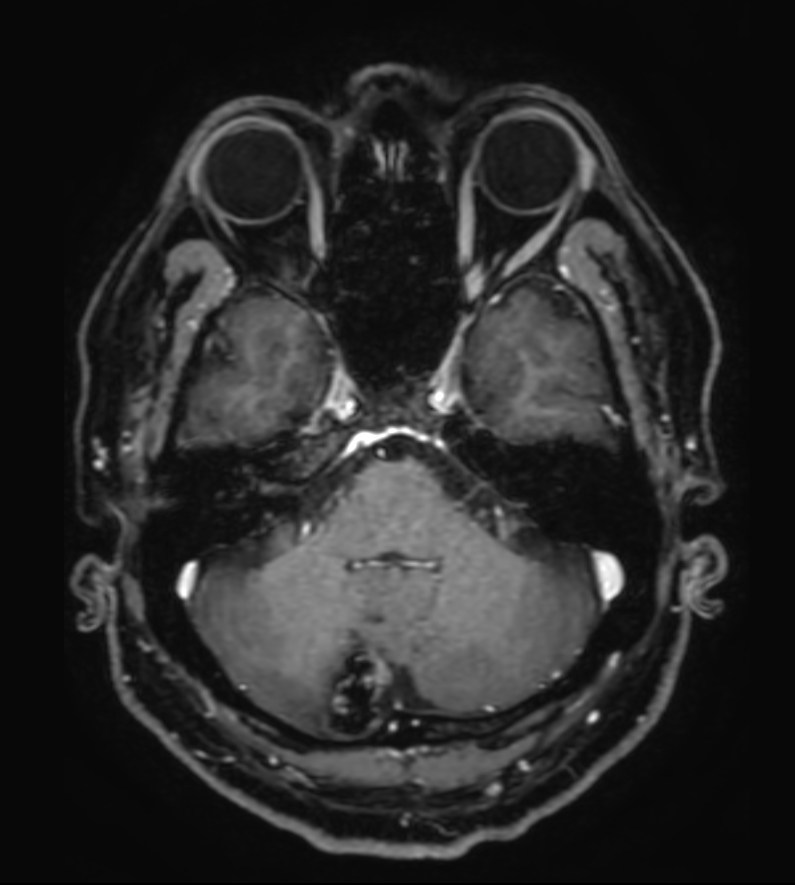

T2w TSE MultiVane XD

Patient with a lesion in the cerebellum. The ExamCard includes Compressed SENSE to accelerate the entire exam and techniques for motion reduced imaging (MultiVane XD), 3D imaging to acquire high resolution data in multiple directions, 3D susceptibility weighted imaging (SWIp), angiography sequences (Time-of-Flight and Contrast-Enhanced MRA with both arterial and venous phases), DTI with MultiBand SENSE to acquire a high number of diffusion directions in a short scan time and EPIC Brain to bring down any residual distortion.